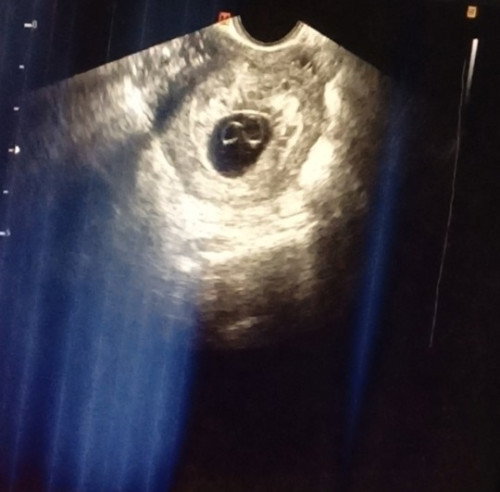

Current 5weeks and 6D based sa LMP. Medyo naninibago ako kasi si lo ay 4yo na. So parang perstaym na naman. Para akong laging hinihingal. Tpos nangangasim. Diko na maalala kung ganito dn ako sa panganay ko. 🥲 Yung sa PT ko naman hndi pa msyadong clear yung second line. Possible na mga nsa 3weeks palang tlga si baby. Grabe ang early pregnancy symptoms ko ngayon. Gusto ko lng lagi matulog. Kayo mga mami? Kamusta ang first term. #sharing